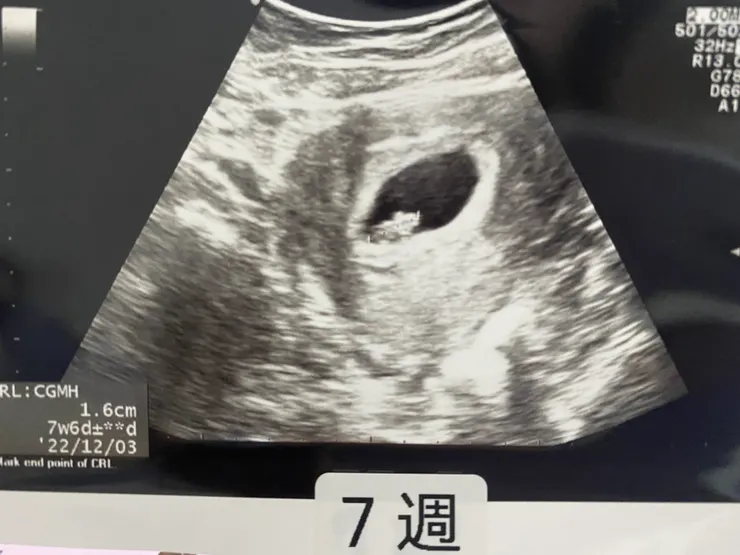

第二趟去婦產科是在懷孕7週,先生一起陪同,

進到診間就直接去超音波室,小生命長得又不一樣了(如圖囉),也聽到奇妙的心跳聲。然後又得到小禮物,孕媽咪手冊。